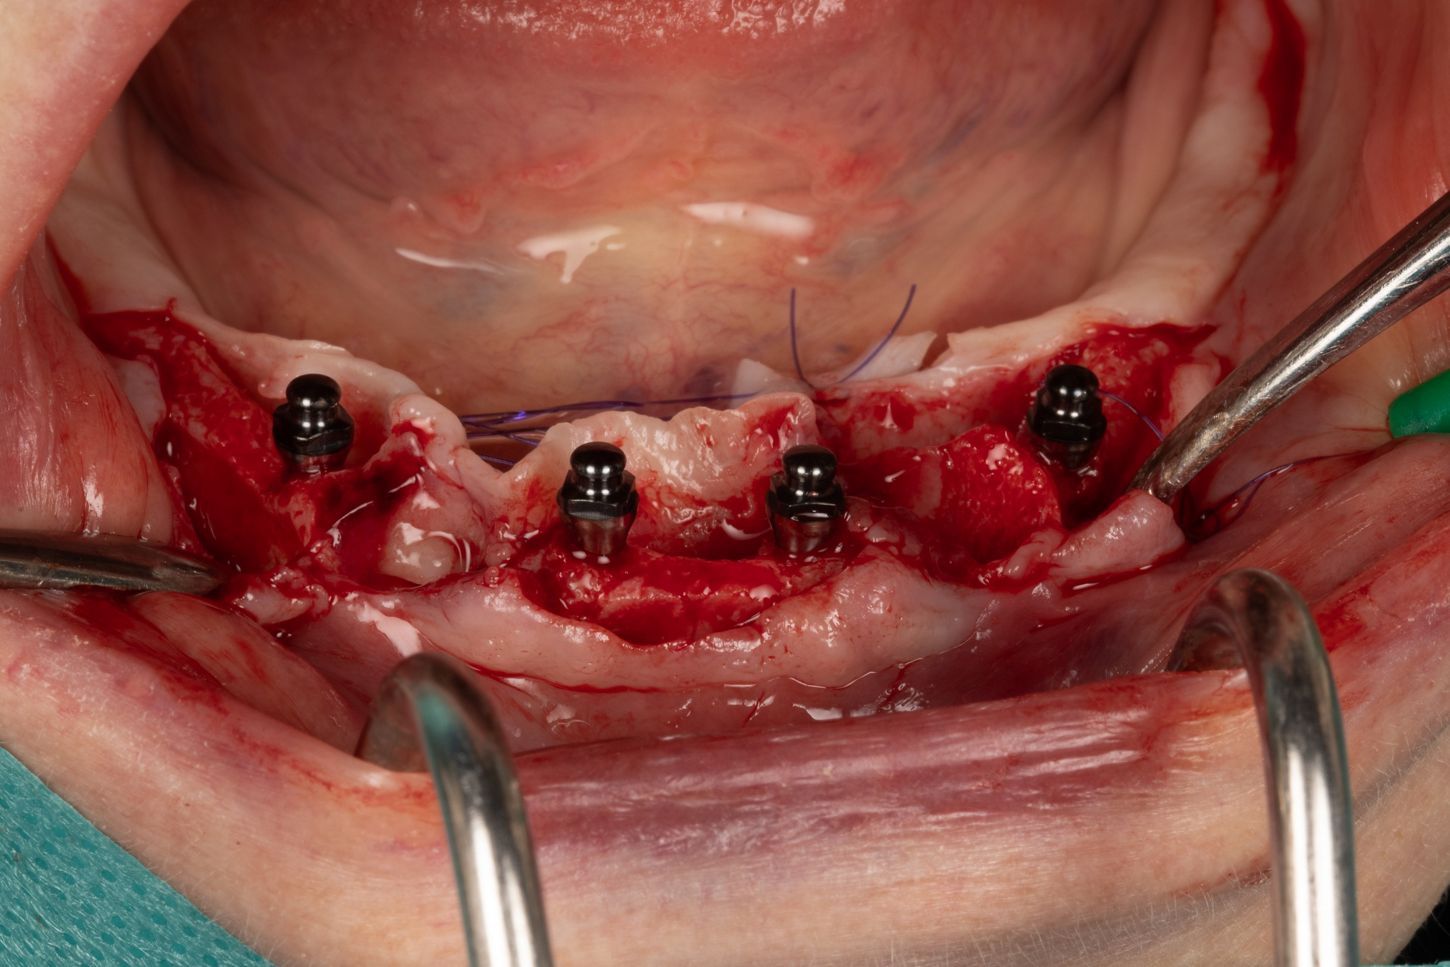

3a. Elevation of the full-thickness flap by crestal incision centred on the keratinised and sulcular tissues in 33 and 43.

The canines are preserved to provide an indication of the drilling axis.

Initial drilling in 32 and 42 using the first 1.5 mm drill bit, then positioning of directional indicators to assist with subsequent drilling. Drilling to 12 mm is checked using the graduation on the initial drill bit.

3a

3b

3b. Drilling adjacent to the remaining teeth 33 and 43 using the initial 1.5 mm drill. Depth and axis checked using the anterior indicators and residual canines.

Given the average bone density (D2 to D3), only the initial drill was used to the working length of 12 mm.

3c. Two mini-implants with a diameter of 2.6 mm and a length of 12 mm were placed in positions 32 and 42, first manually and then using a contra-angle. The insertion torque recorded at the end of the procedure was 21 N.cm in 32 and 17 N.cm in 42. The implants were positioned 0.5 mm subcrestal, i.e. with slight burial of the smooth neck.

3c

3d

3d. Two mini-implants with a diameter of 2.6 mm and a length of 12 mm were placed in positions 34 and 44 using the same protocol as for the previous mini-implants. The torque obtained was 27 Ncm in 34 and 37 Ncm in 44.

3e. Canines 33 and 43 were extracted and the burial of the implants was then checked.

3e